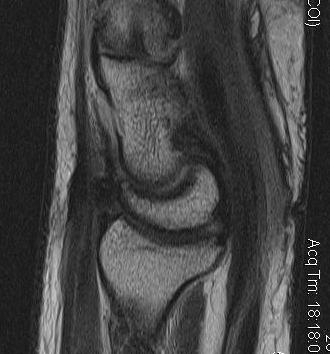

MRI

Can demonstrate tear

- need experienced radiologist

- need MRI in correct plane

- sensitivity may be as low as 40%